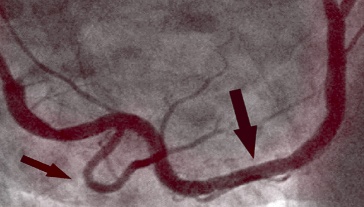

NAKON TERAPIJE

Na slici desno vidimo očišćenu desnu koronarnu arteriju već bez tragova kalcificiranog aterosklerotskog plaka kod istog pacijenta nakon 1. mjeseca terapije. Nema smrtonosnih naslaga kolesterola. Krv teče slobodno, opskrbljujući kisikom sve organe.